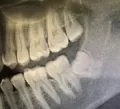

Сделав рентген, врач сказал, что требуется вмешательство стоматолога-хирурга. Так как 8-й зуб уперся в 7-й и именно это является причиной боли. С этим я с ним согласен. Но он сказал, что рано или поздно придется делать операцию и удалять 8-й зуб, так как он сам не прорастет. И главное он говорил, так как будто нет шансов, что зуб сам сможет прорасти.

Действительно, Ваш зуб самостоятельно прорезаться не может, потому что он "лежит" по направлению к 7-му зубу, самостоятельно он может двигаться только в сторону 7-го.